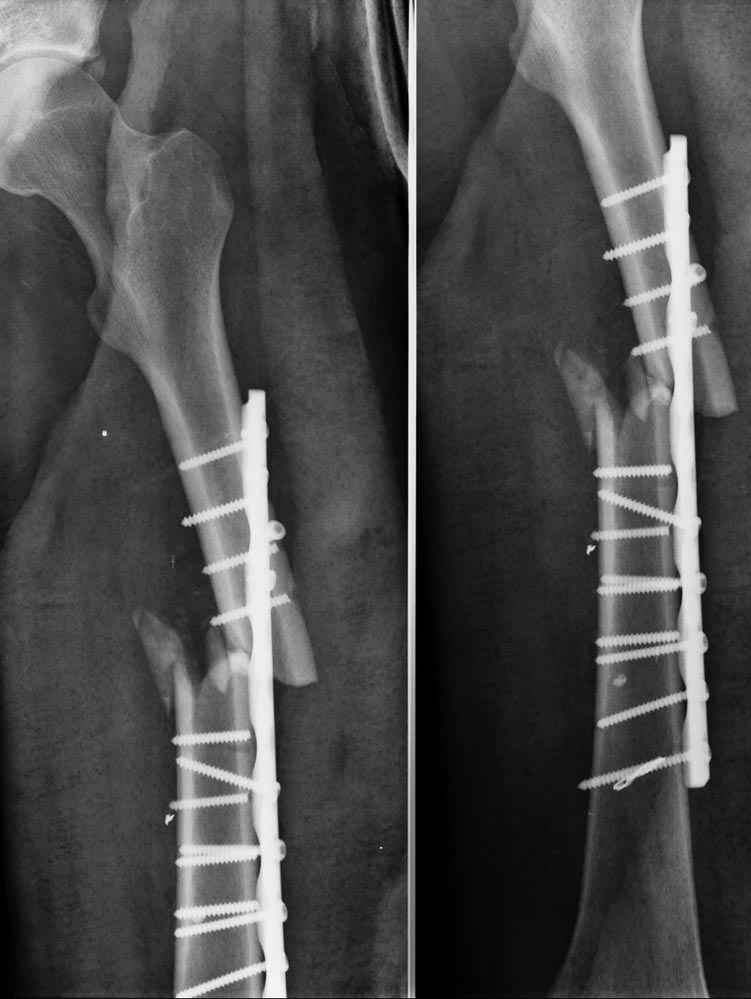

Доброго дня уважаемые коллеги! Пациент Г 28 лет травма при ДТП от 11.07:

ЗЧМТ (сознание не терял). Закрытый перелом левой бедренной кости,

закрытые переломы большеберцовой кости и шейки таранной кости слева.

14.07 выполнен МОС левого бедра пластиной, фиксация левой

голени и стопы в АВФ. 18.07 при попытке вертикализации отметил сильный

спазм и боль в области левого бедра (на снимках перелом по шейкам 4-х

дистальных винтов). В этот же день реостеосинтез левого бедра,

дренирование раны (дренаж почему то держали до 25.07). Выписан

домой. 26.07 при повороте в постели повторный спазм и боль. На снимках

опять же перелом дистальных винтов. При личной беседе пациент более чем

адекватен, без сопутствующей соматической патологии. Фраза "сам виноват"

к нему очень подходит. Возникало мнение о какой-либо форме столбняка,

может гиперактивности каких-либо L-мотонейронов, но все из

рода больше казуистики. А может все проще: тонкие винты, "мало"

отверстий в пластине, сам пациент...